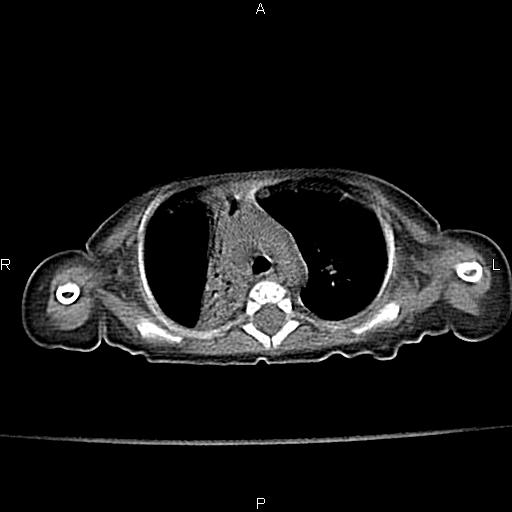

以下是引用aa13877358820在2010-7-26 12:35:00的发言:[br]男性,三个月,卧位胸片,咳嗽、气促、发热14天,两肺闻及细小水泡音。[br]